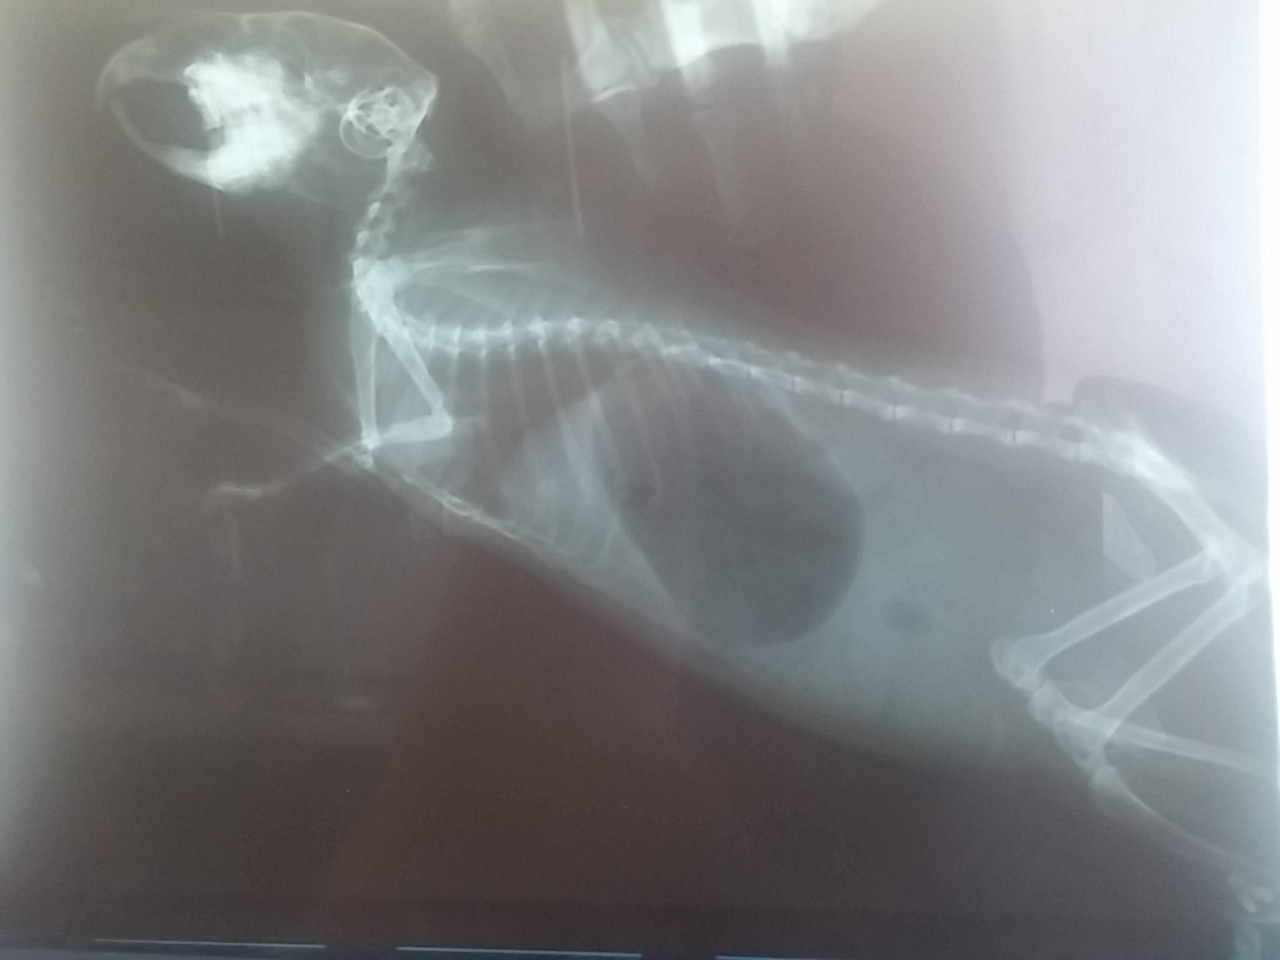

Nasza świnka już praktycznie się dziś nie rusza - ma płytki oddech i przymknięte oczy... Wrażenie jak by w stanie agonalnym była! Powiedziałam mężowi by jechał ją uśpić bo już nie mogę na to patrzeć...Mąż pojechał do swojego kolegi weterynarza. Po opisaniu sytuacji - kwestii nie jedzenia, przycinania trzonów, oraz podejrzenia zwichnięcia szczęki - Kolega mojego męża zapytał czy miała robione RTG.

Świnka nie miała gdyż gdy się pytałam u weterynarza w Poznaniu gdzie miała robiony zabieg - powiedzieli że i tak by nic nie było widać czy sa ropnie i czy jest zwichnięta szczęka więc nie było sensu. Pani doktor wyczuwa podobno ropnie i zwichnięcie szczęki, badając dotykiem. Weterynarz to Pani doktor Cichoszewska w Poznaniu - polecany wet na świnkowym portalu.

Znajomy męża jednak stwierdził że on zrobi te RTG dla świętego spokoju, i wtedy zobaczymy... Po zrobieniu zdjęcia, okazało się że szczęka ma się dobrze - zęby ładnie przycięte - a dlaczego nie je i jest taka osowiała ? Ma potężne wzdęcie - żołądek wielkości mniejszego kiwi! Płytki oddech spowodowany jest tym że każde nabranie powietrza sprawia jej ból i ucisk. Tez przez ostatni 2-3 dni wydawała is ie jakaś taka grubsza - już wiem dlaczego.

Kolega nakazał biegnąć do apteki po Bobotic i Cebion 2x dziennie po 0,2ml. Mówi że powinno zejść to w przeciągu 2-3 dni. I wtedy zobaczymy jak z jedzonkiem. Tak więc nasza świnka całe szczęście jest nadal z nami i walczymy dalej... niestety cały czas powoli chudnie - ma już z 550gram.

12.jpg